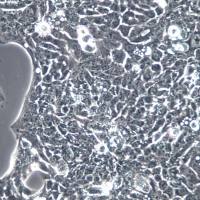

SH-SY5Y

脑神经母细胞瘤,转移部位骨髓

人

贴壁,悬浮均有;上皮细胞样

悬浮淋巴母细胞样